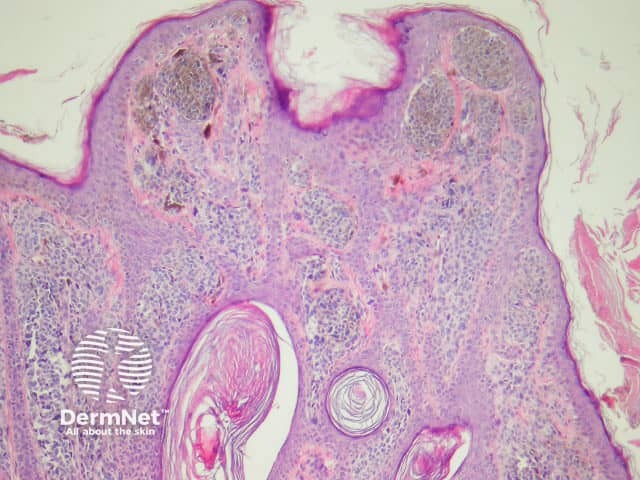

The histological features of SCC in situ (intraepidermal carcinoma) show extensive overlap with actinic keratosis and are:

Pathology of squamous cell carcinoma in situ